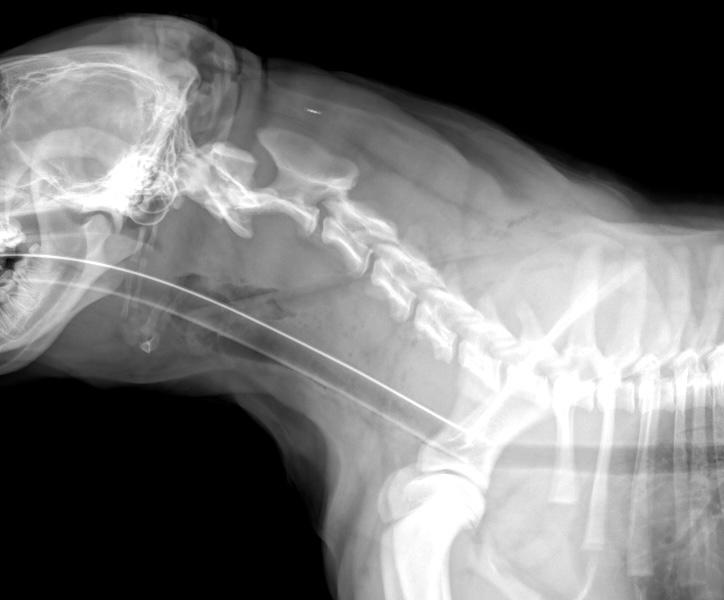

Klarheit durch eine Röntgenaufnahme

Eine Röntgenaufnahme sollte Klarheit über die Schwere der Verletzung schaffen. Da „Baby Kyro“ ganz offensichtlich üble Schmerzen hatte, musste er zuerst sediert und – als Sicherheitsmassnahme – intubiert werden, bevor das Röntgenbild gemacht werden konnte.

Beim Einführen des Atemschlauches in die Luftröhre stellte der Arzt eine Verletzung im hinteren Rachenraum fest. Und als die Röntgenaufnahme im Bereich zwischen Rachen und Schulter eine dunkle Struktur aufzeigte, lag die Vermutung nahe, dass sich der Holzstecken beim Spielen durch den Rachen in die Schulter gebohrt hatte.